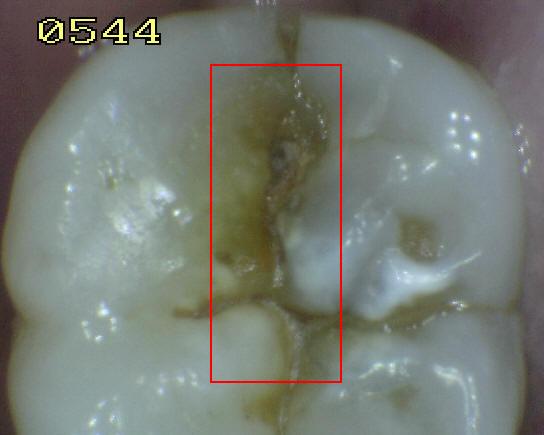

Código 5:

Cavidad detectable con dentina visible hasta la

mitad de la superficie

- Hay una cavidad en el esmalte opaco

o decolorado, dejando al descubierto la dentina. El diente

visto en estado húmedo puede haber oscurecimiento de la

dentina visible a través del esmalte. Una vez seco, hay

evidencia visual de la pérdida de la estructura del diente a la

entrada o dentro de la fosa o fisura, cavitación franca

> 0,5 mm hasta la mitad de la superficie dental. Hay evidencia visual de

desmineralización ( blanco opaco, de color marrón o paredes negras

ó de color marrón) en la entrada o dentro de la fosa o fisura. A juicio

del examinador se observa dentina expuesta en el piso y paredes de la

cavidad.